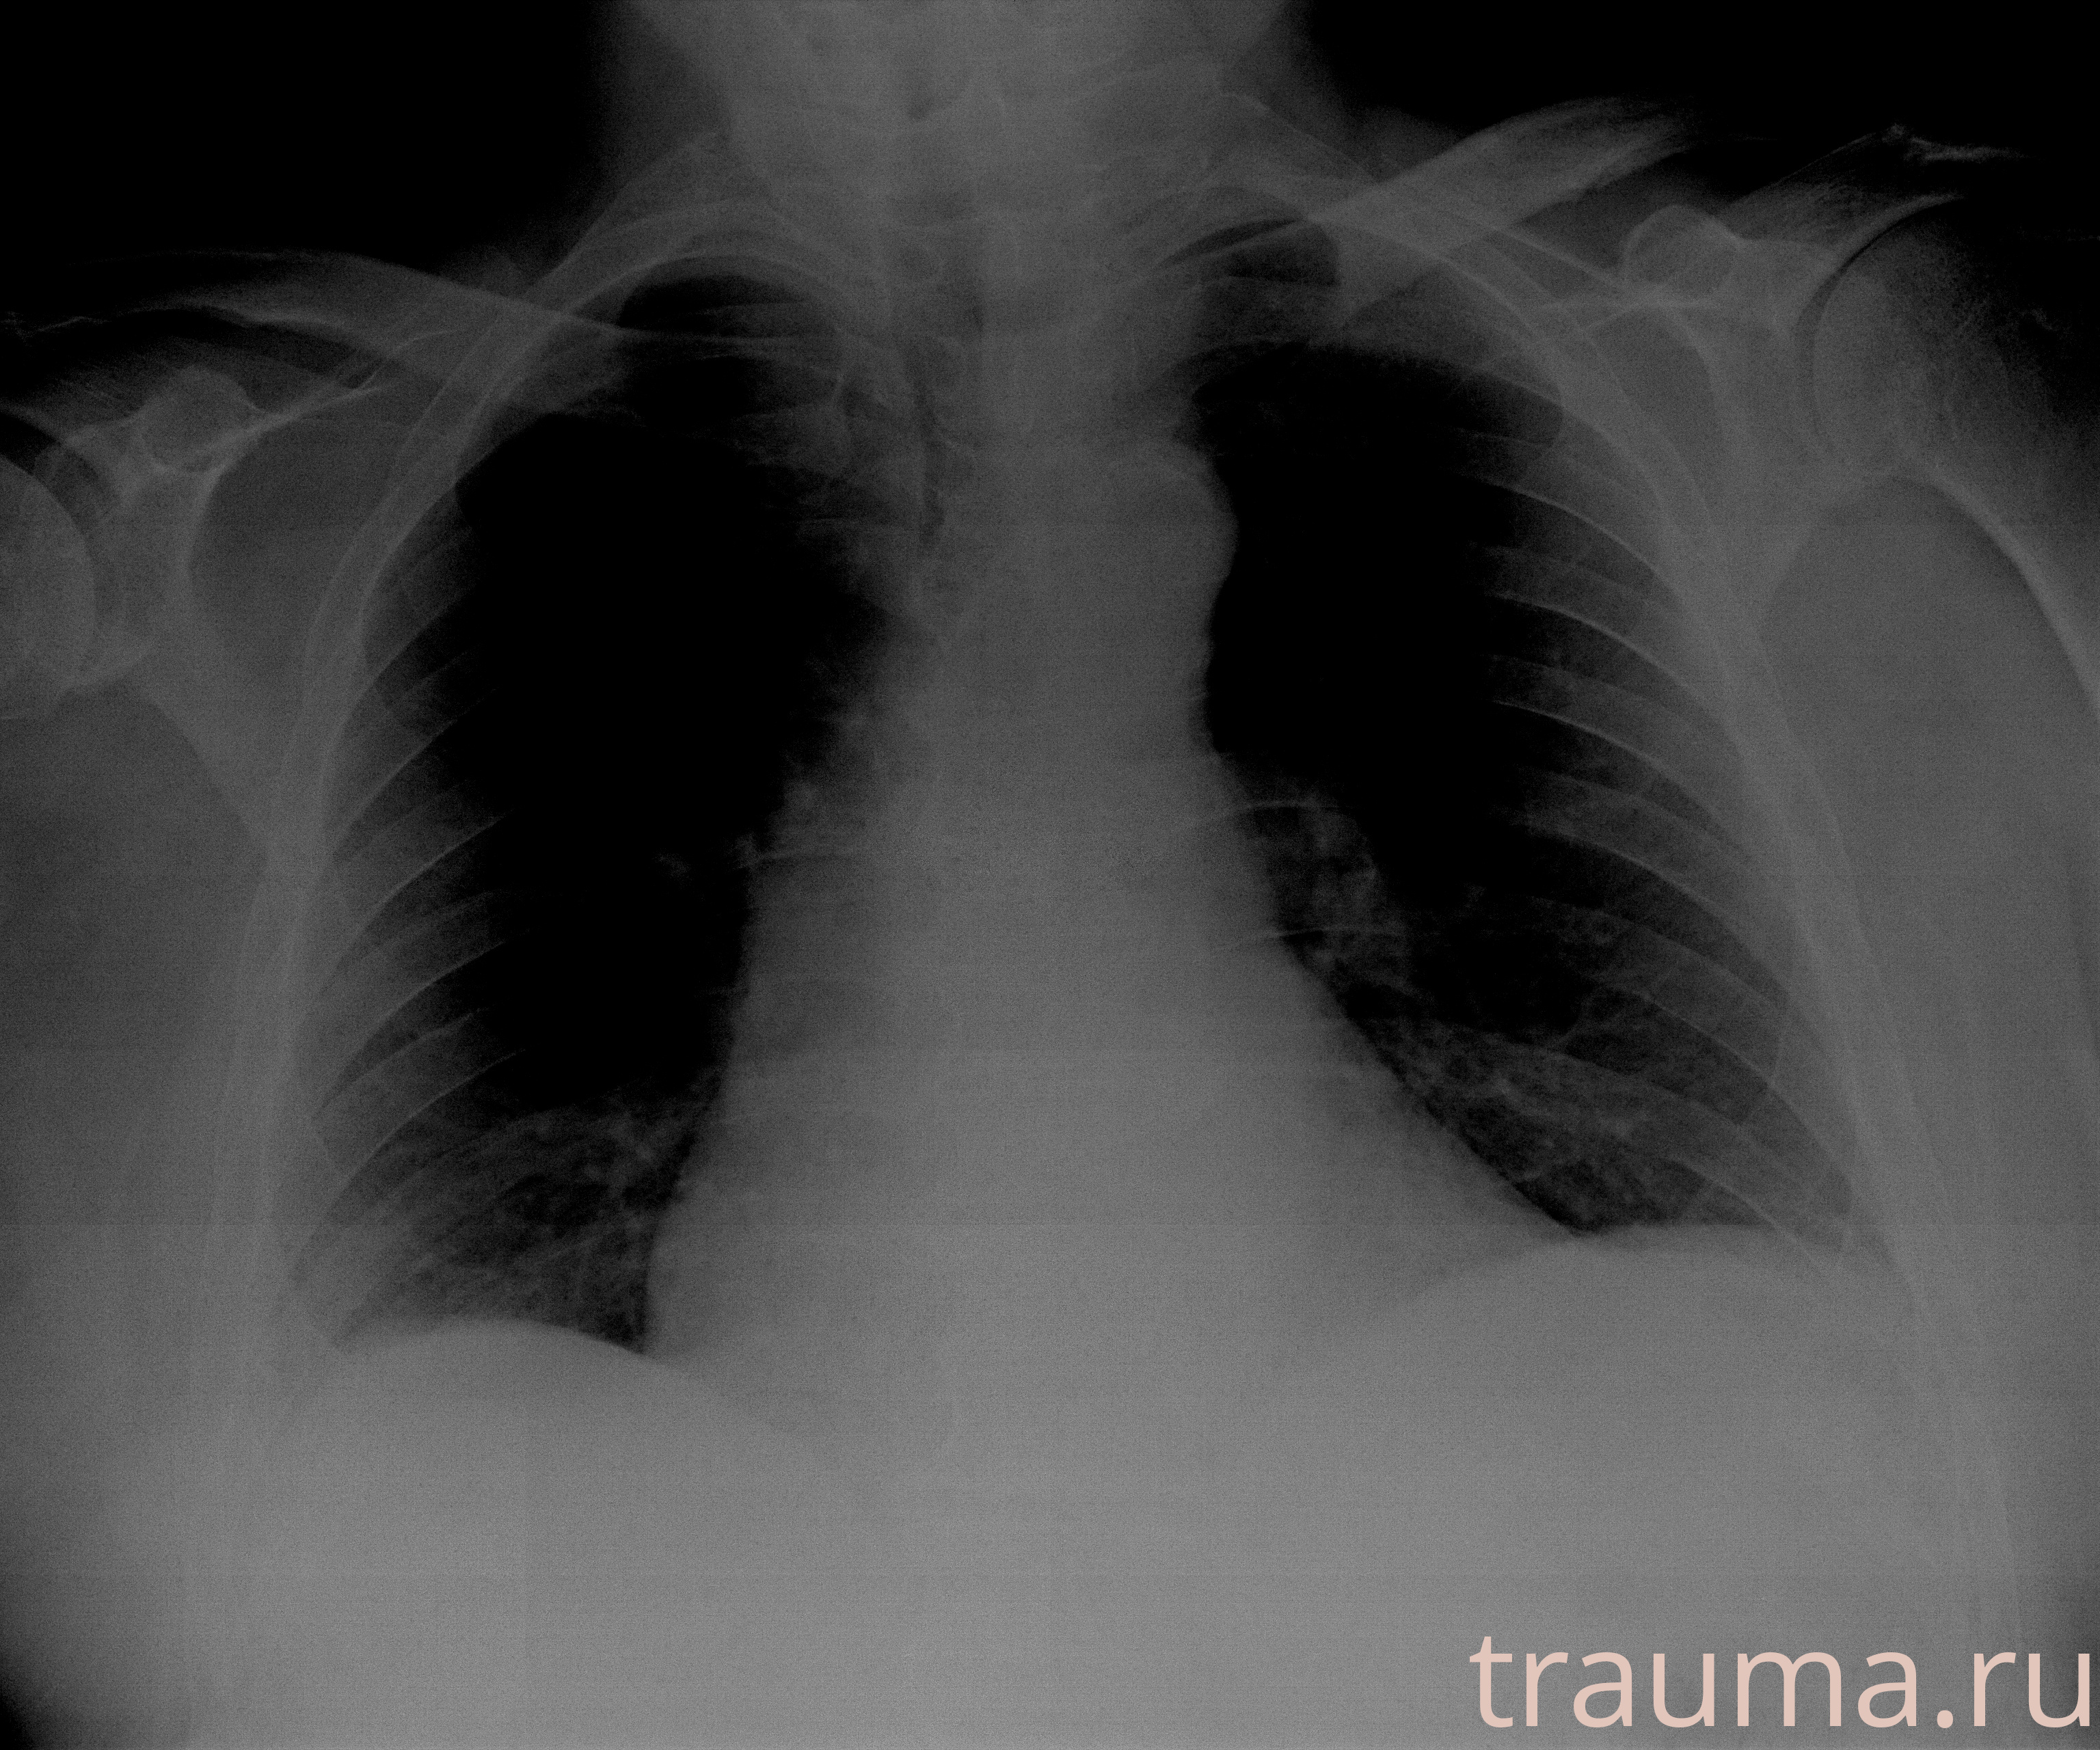

Рентген на дому: по вашему адресу приезжает врач-рентгенолог, травматолог-ортопед с мобильным рентгеновским аппаратом, проводит диагностику травмы или заболевания, делает необходимые рентгенограммы, дает рекомендации по дальнейшему лечению. Получить качественные снимки в домашних условиях возможно благодаря уникальной методике, разработанной МосРентген Центром для института  Склифосовского